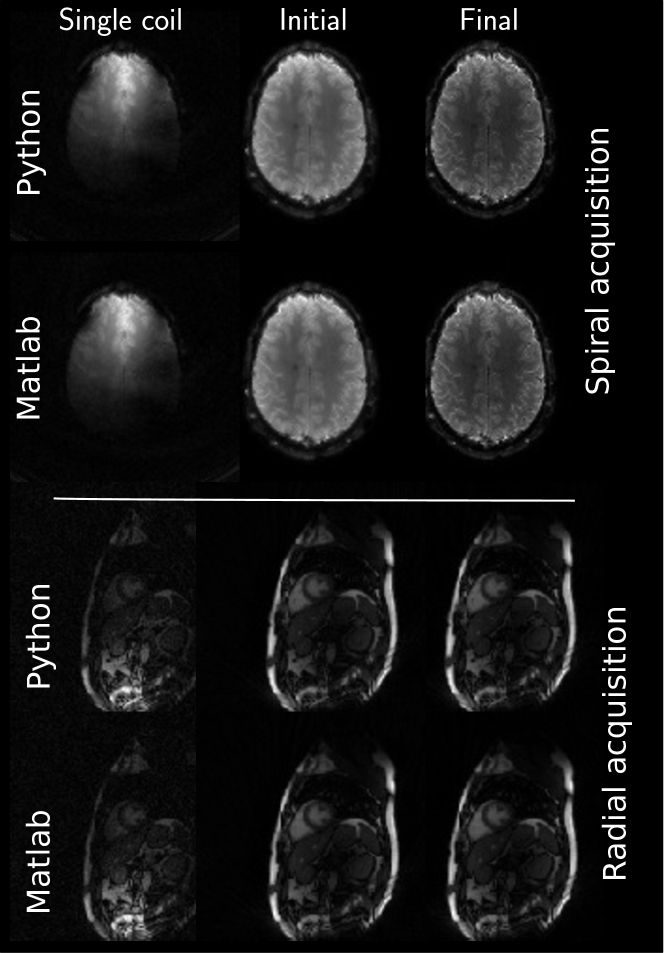

The pixel-wise comparison between the two reference implementations in Figure 8 for brain (top part) and heart (bottom part) data shows the overall excellent accordance between the Matlab and Python reconstruction results. No major differences are visible in any of the images. The single coil images and initial images show very slight intensity differences. The visual impression is supported by high SSIM values (0.9987-0.9998) and small NRMSE values (0.006-0.028). The highest differences are visible outside of the brain at the border of the used image mask. Similar excellent accordance between both reconstructions is achieved for heart data. NRMSE and SSIM are comparable to the brain data but areas with little to no signal outside the body show slight, noise-like deviations.

Finally, Figure 9 shows the two additionally supplied data sets. Both reference methods are able to produce clean images and visually, no differences can be observed.

Figure 8: Relative pixel-wise difference between the Matlab reference reconstruction results and the Python reference implementation. To account for different intensities, all images were normalized prior to the difference operation. SSIM and NRMSE values between the two references are given next to each image. Metrics are computed from values within a binary mask, containing the brain and heart, respectively.

Figure 9: Example reconstruction results of the two additional supplied data sets. Top rows show the spirally acquired brain data set and bottom rows show radially acquired cardiac data. Both reconstructions included noise pre-whitening prior to reconstruction from a dedicated noise scan preceding image acquisition. Windowing is performed between the minimum and maximum intensity value in each image.